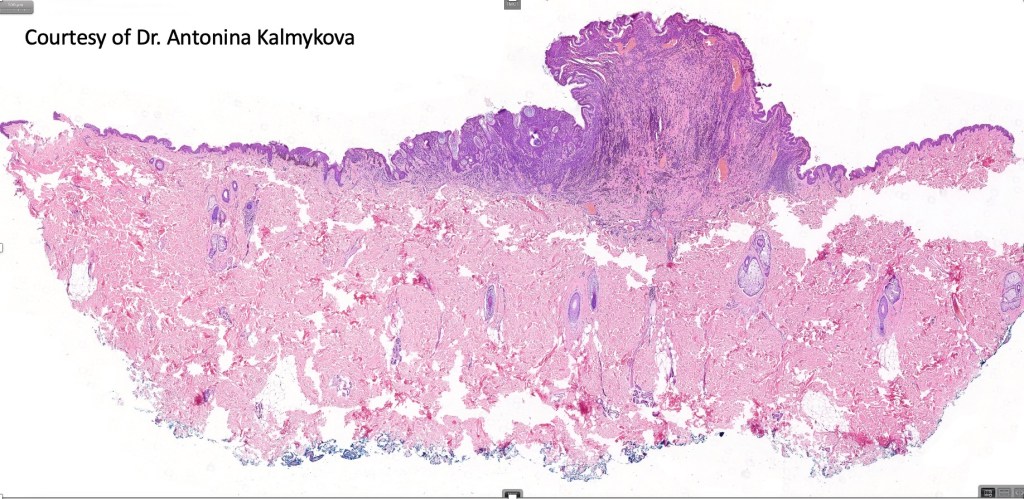

This is uncommon and presents clinically with a history of recent change in color of a common or less often congenital nevus causing concern for melanoma by the clinician. Some, but not all are probably deep penetrating and combined nevus variants. Others may represent follicular type-A cell nests. It is characterized by the presence of deep nest(s) of type -A nevus cells surrounded by & with overlying type-B nevus cells.